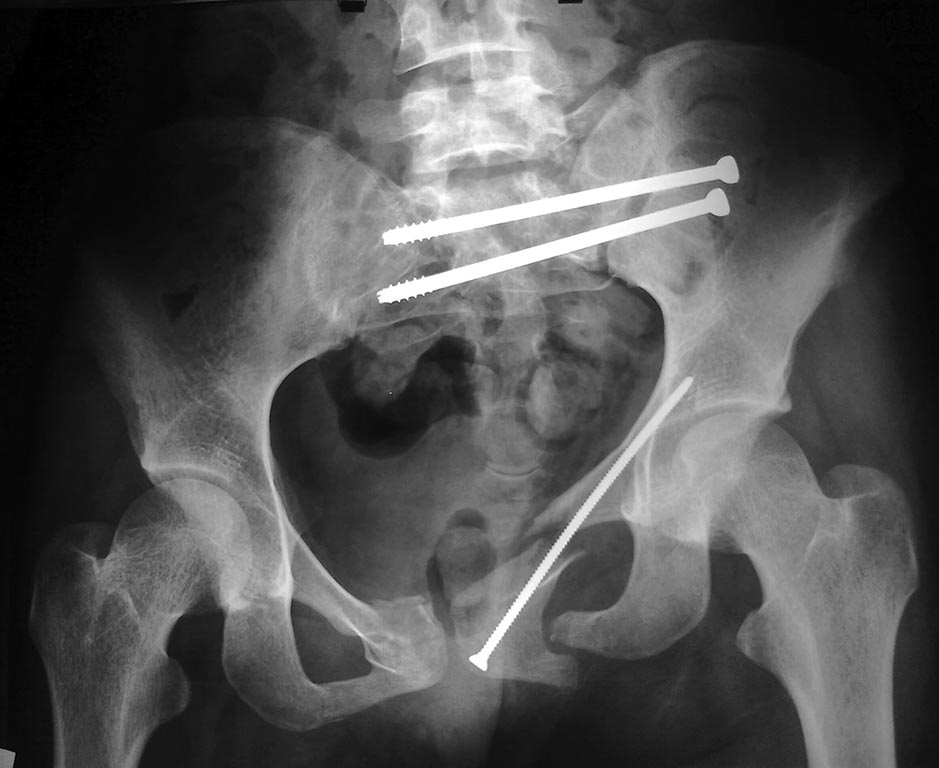

Сегодня мы имеем вот такой таз!Девушка 23г .Укорочение 4 см.

Давность травмы 5 нед, остеосинтез проведен к концу второй недели. КТ не получается отправить на диске, хитрая программа - не копирует. Вся боковая масса крестца, где илиосакральные винты, в мелких осколках. Перелом поперечного отростка 5 поясничного позвонка, в него так и упирается крыло. Неврологии нет.

Наверное стоит делать реостеосинтез

Добрый вечер! данное повреждение классифицируется как унилатеральное вертикально нестабильное повреждение тазового кольца,крестец сломан трансфораменально поэтому с такой степенью смещения, неврология скорее всего, есть, нужно проверить иннервацию промежности, перианальной области, задней поверхности голени, недержание мочи, кала (часто приписывают дисбактериозу на фоне приема антибиотиков). путе решения несколько: 1. перевести пациентку в профильное учреждение где данные операции на потоке. Если возметесь сами, то можно использовать варианты: 2. удаление всех конструкций, устранение деформации в кольцевом аппарате Рункова, с последующим илиосакральным блокированием 2 винтами 7,3 мм с полонрезьбовой нарезкой, чтобы не создать в области перелома компрессии корешков. переднее полукольцо лучше фиксировать реконструкционной пластиной,т.к. скомпроментированы обе ветви лонных костей, и, не исключено, что поврежден симфиз. Возможна и одномоментная коррекция: 3 Удаление конструкций, заний доступ низведение половины таза и илиолюмбальная (дистантная) стабилизация транспедикулярной конструкцией III-IV позвонки - 1-2 винта в крыло таза (осторожно у худых пациентов возможны проблемы с закрытием конструкции мягкими тканями) все это обязательно дополнить позиционным илиосакральным винтом 7.3 мм переднее полукольцо см выше. Есть еще вариант реконсрукции через подвздошно-паховый доступ с последующим артродезом малыми пластинами, но это проблематичнее т.к. толкать легче чем тянуть на себя, ограниченная площадь для позиционирования малых пластин из-за близости нервных стволов, да и винты малого диаметра менее надежны. Ну примерно как-то так. С уважением Ушаков СА

Безусловно согласен со всеми авторами, что необходимо исправлять тазовое кольцо. Конечно 5 недель после травмы и 3 недели после операции срок уже не маленький, но вполне реальный для реостеосинтеза. При переломе боковых масс крестца, после репозиции, необходима фиксация винтами со сплошной резьбой (фиксация по типу позиционного винта), а при выполненном способе фиксации, боковые массы крестца стянуты и крепко фиксированы, в нерепонированном состоянии, всвязи с этим и расхождение отломков лонной и седалищной костей, и то, что нет неврологии - только вопрос времени, она появится по мере консолидации перелома крестца. Передний отдел я бы фиксировал тазовой реконструкционной пластиной после, точной репозиции, через небольшие разрезы, проведя её малоинвазивно, хотя на данном этапе через малые разрезы уже наврядли получится, но думаю это уже не самаябольшая проблема.